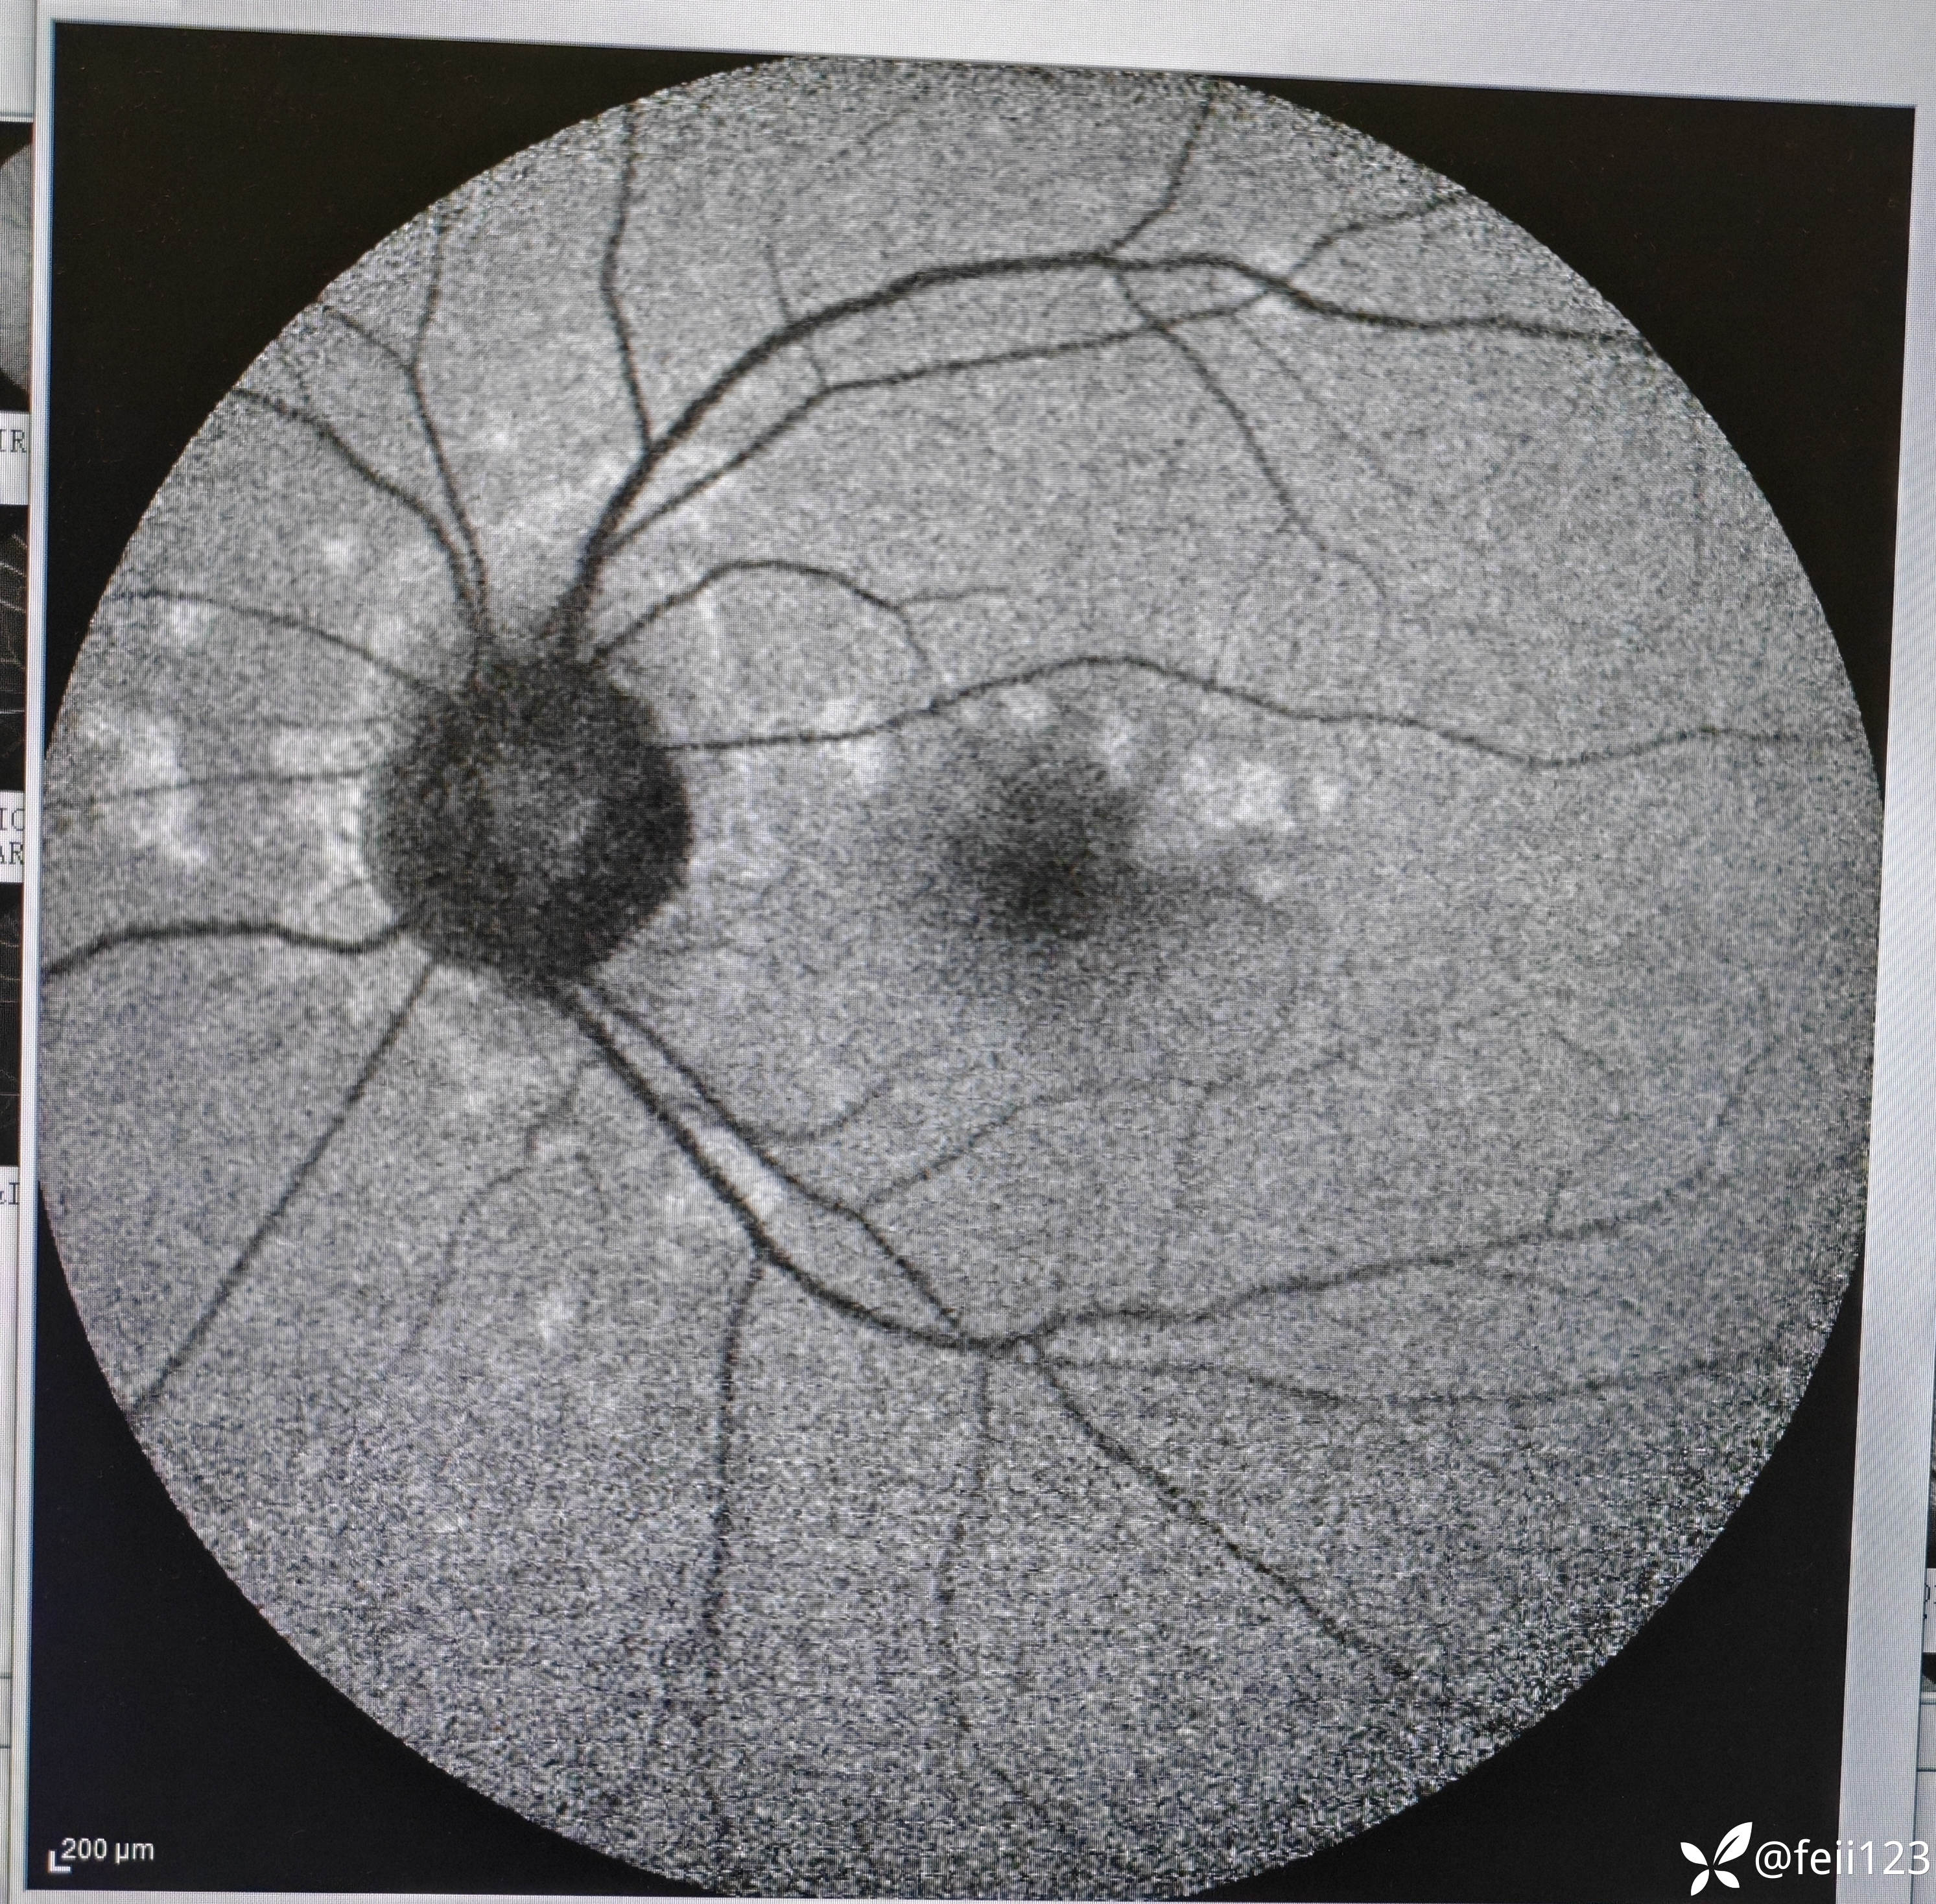

【检查】矫正视力右眼1.0左眼0.4,眼压正常15 16,眼前段未见异常,玻璃体清,眼底如图,左眼底可见后极部及鼻侧周边多个白点。